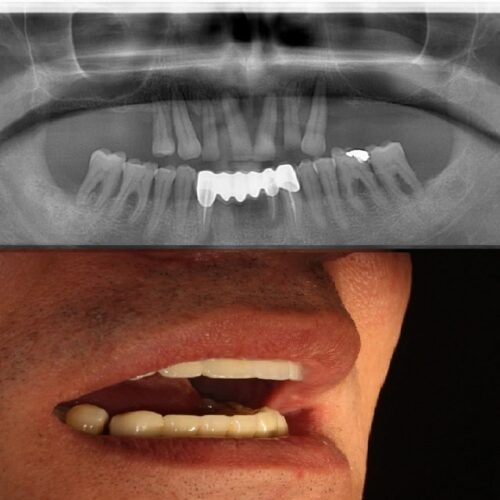

Mini-implanturile dentare sunt mai inguste decât implanturile obișnuite. Acestea sunt utilizate în anumite cazuri în locul implanturilor normale, din motive medicale, financiare sau anatomice. Cel mai frecvent sunt folosite pentru dinții mici, dinții din față, premolarii, dinții din zone înguste sau pentru pacienții la care densitatea țesutului osos este scăzută. Susținând majoritatea tipurilor de dinți de înlocuire, mini implanturile sunt folosite pentru proteze semimobile, punți și coroane fixe. Diferențele dintre mini-implanturi și implanturile obișnuite: Dimensiune – Diferența de dimensiune constă în diametrul implantului. Mini-implanturile dentare măsoară mai puțin de 3 mm în diametru, în timp ce implanturile obișnuite măsoară 3,5-5 mm. Rezistența – deoarece mini-implanturile sunt mai mici, nu pot suporta forța de masticatie pe care o poate suporta un implant obișnuit. Din acest motiv, acestea nu sunt folosite în cazul în care se înlocuiesc molarii. Procesul de vindecare – procesul de încorporare a unui mini-implant dentar este mai rapid decât cel al unui implant tradițional. Acest lucru este valabil și pentru timpul de vindecare.